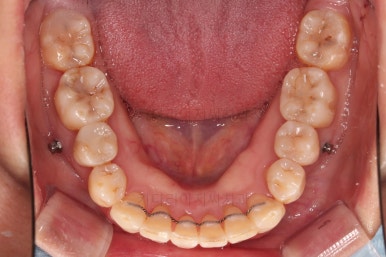

이번에 사용하신 장치는 엠파워 메탈이라고 하는 자가결찰 금속 장치인데요.

금속 재료를 시각적으로 신경쓰지 않으셔꼬 메탈장치가 세라믹에 비해 양치라던지 잇몸에 그래도 약간의 장점이 있어서 추천되기도 했어요.

비발치 치료에서 핵심되는 장치가 미니스크류에요.

위 사진에서도 어금니쪽 잇몸 부위를 보시면 아주 작은 금속성 나사머리가 보이실건데요. 나사로 단단히 지탱해주고 치열을 뒤로 당겨주는 원리죠.